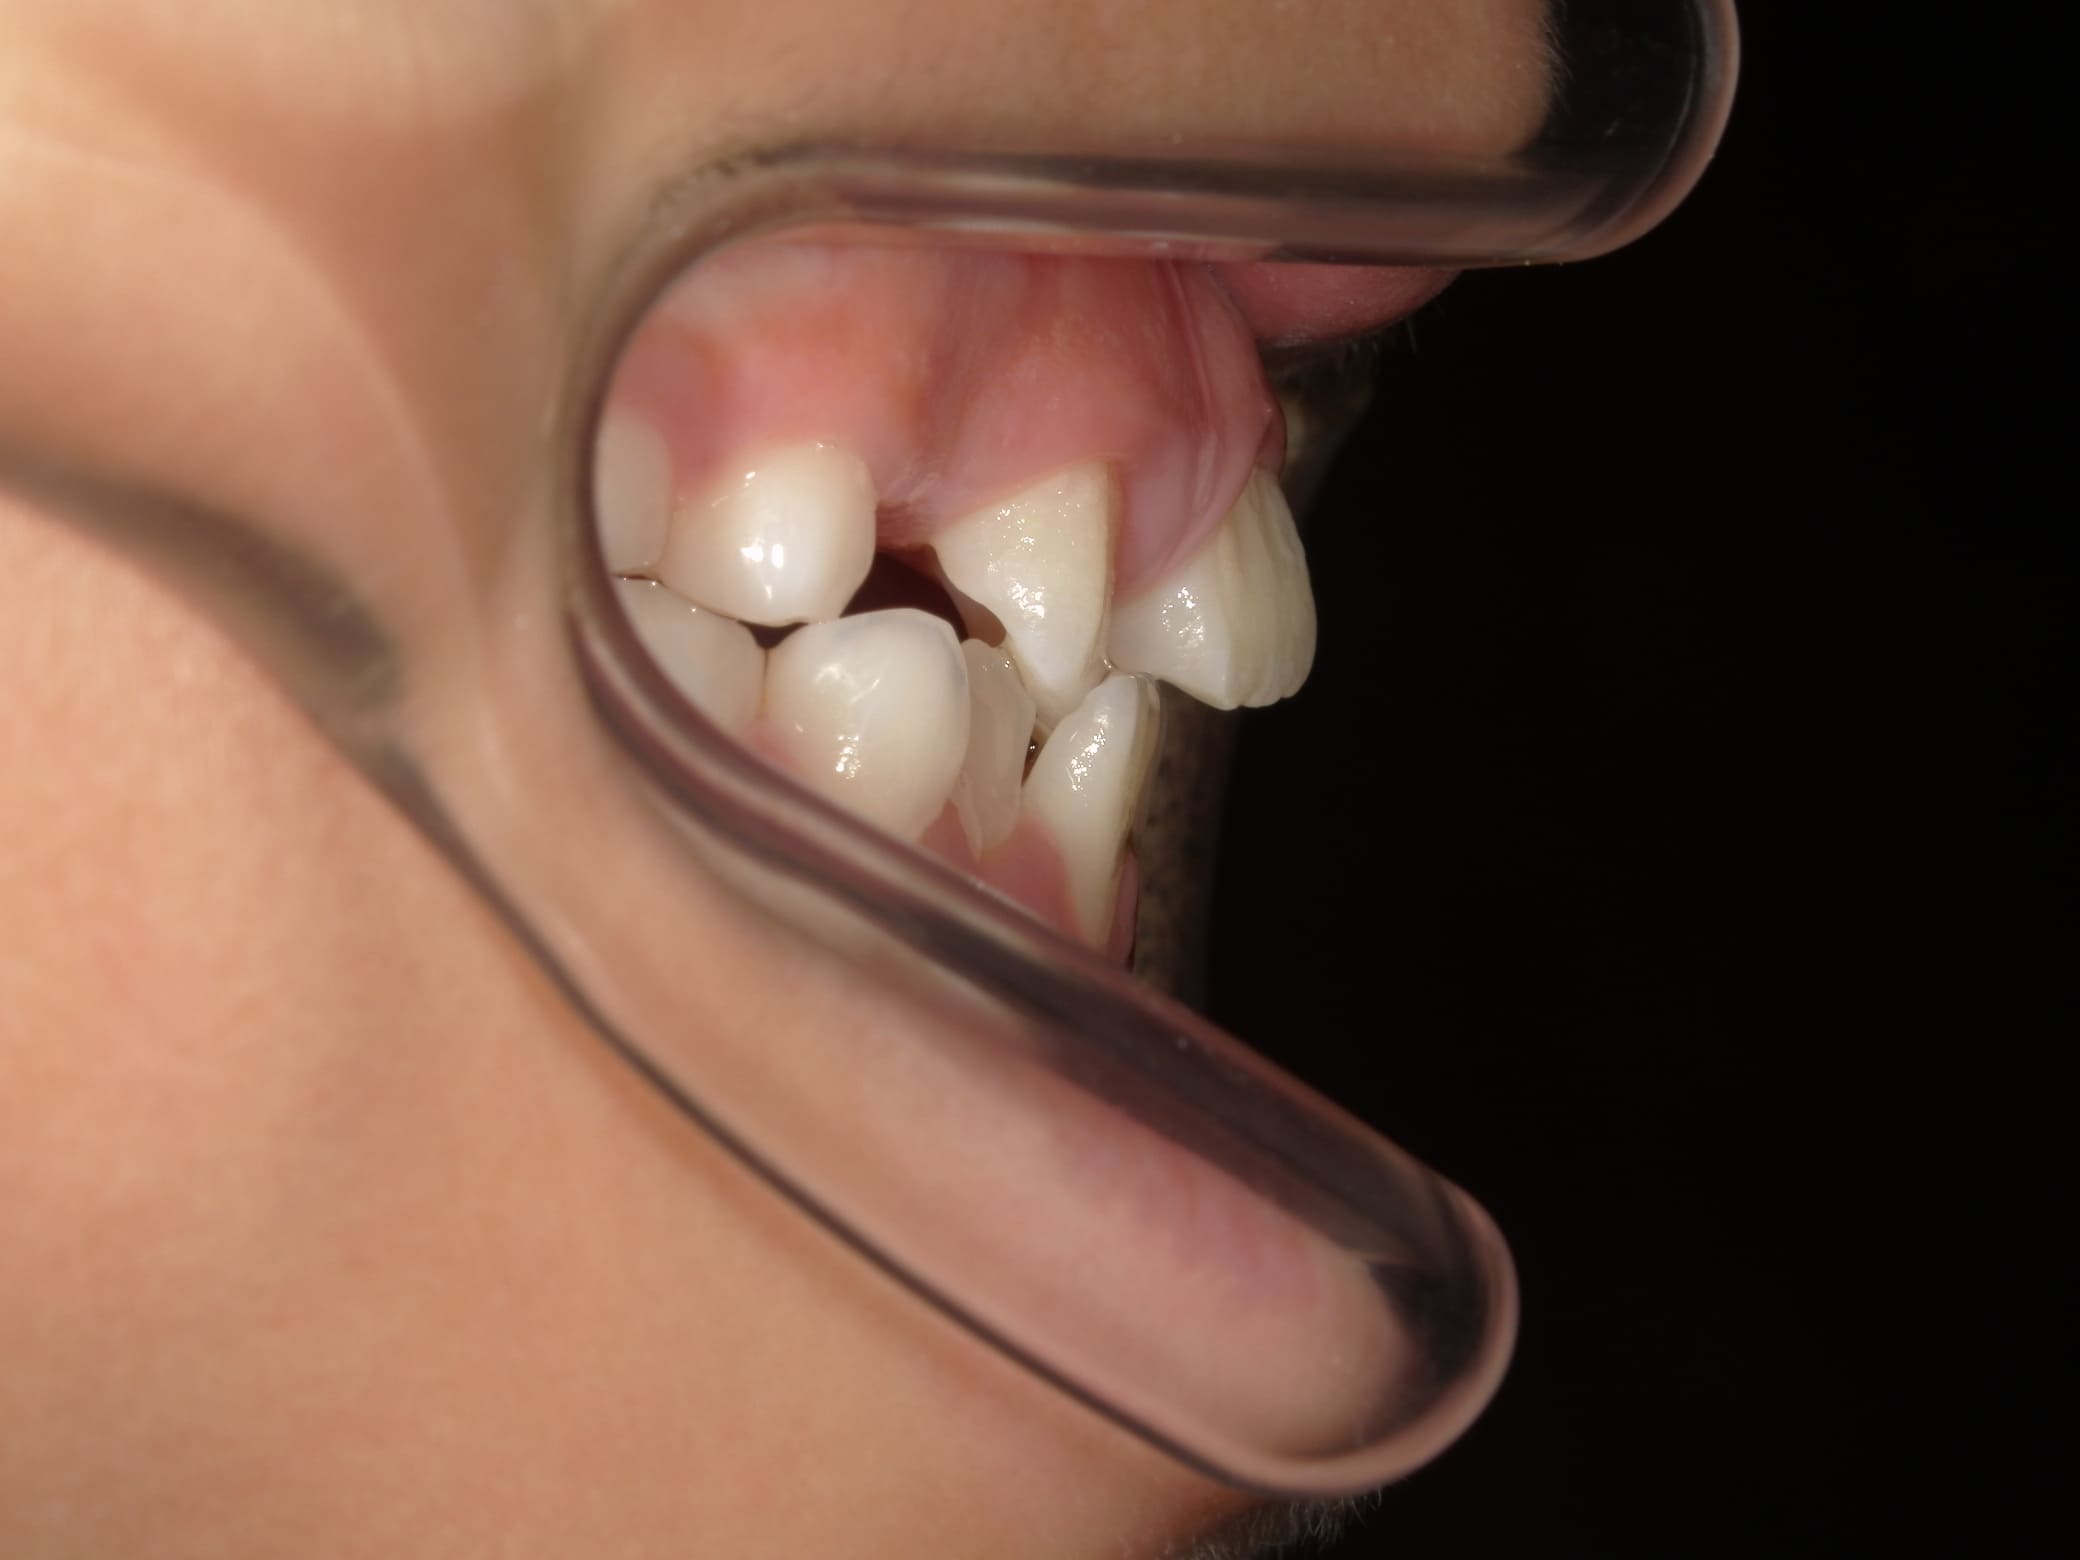

| 年齢・性別 | 8歳9ヶ月の女児 |

|---|---|

| 主訴 | 歯並びの乱れを気にされて来院された患者様です。将来的なスペース不足と歯のねじれ(翼状捻転)が懸念されました。 |

| 治療期間・回数 | 2年10ヶ月・19回 |

| 費用 | 430,000円(税別) |